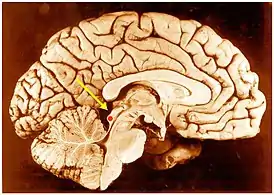

![]() Нижние холмики четверохолмия в головном мозге человека. Сагиттальный разрез. | |